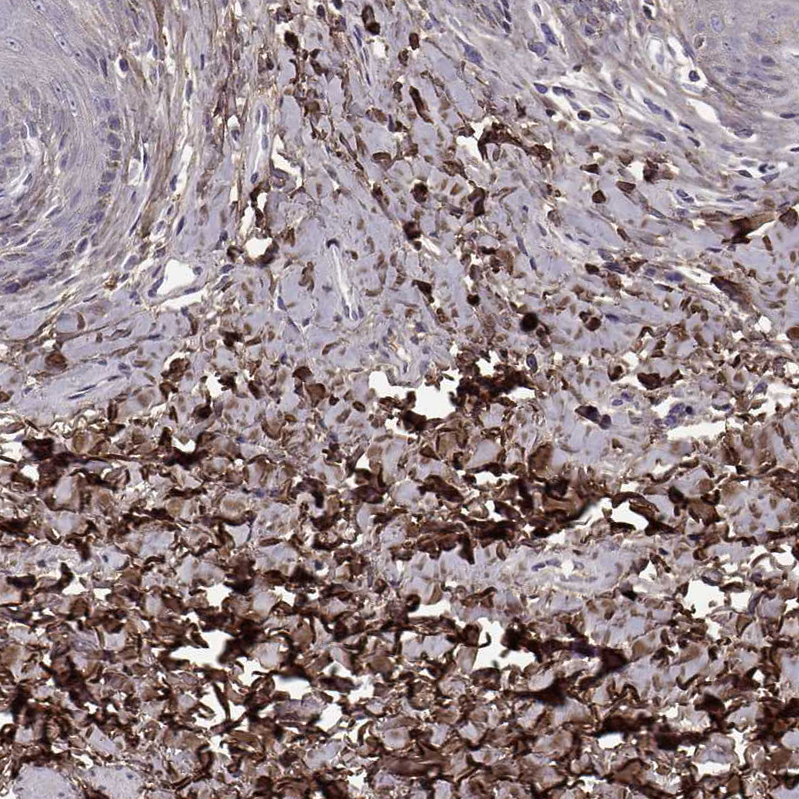

Immunohistochemical staining of human breast shows moderate to strong cytoplasmic positivity.